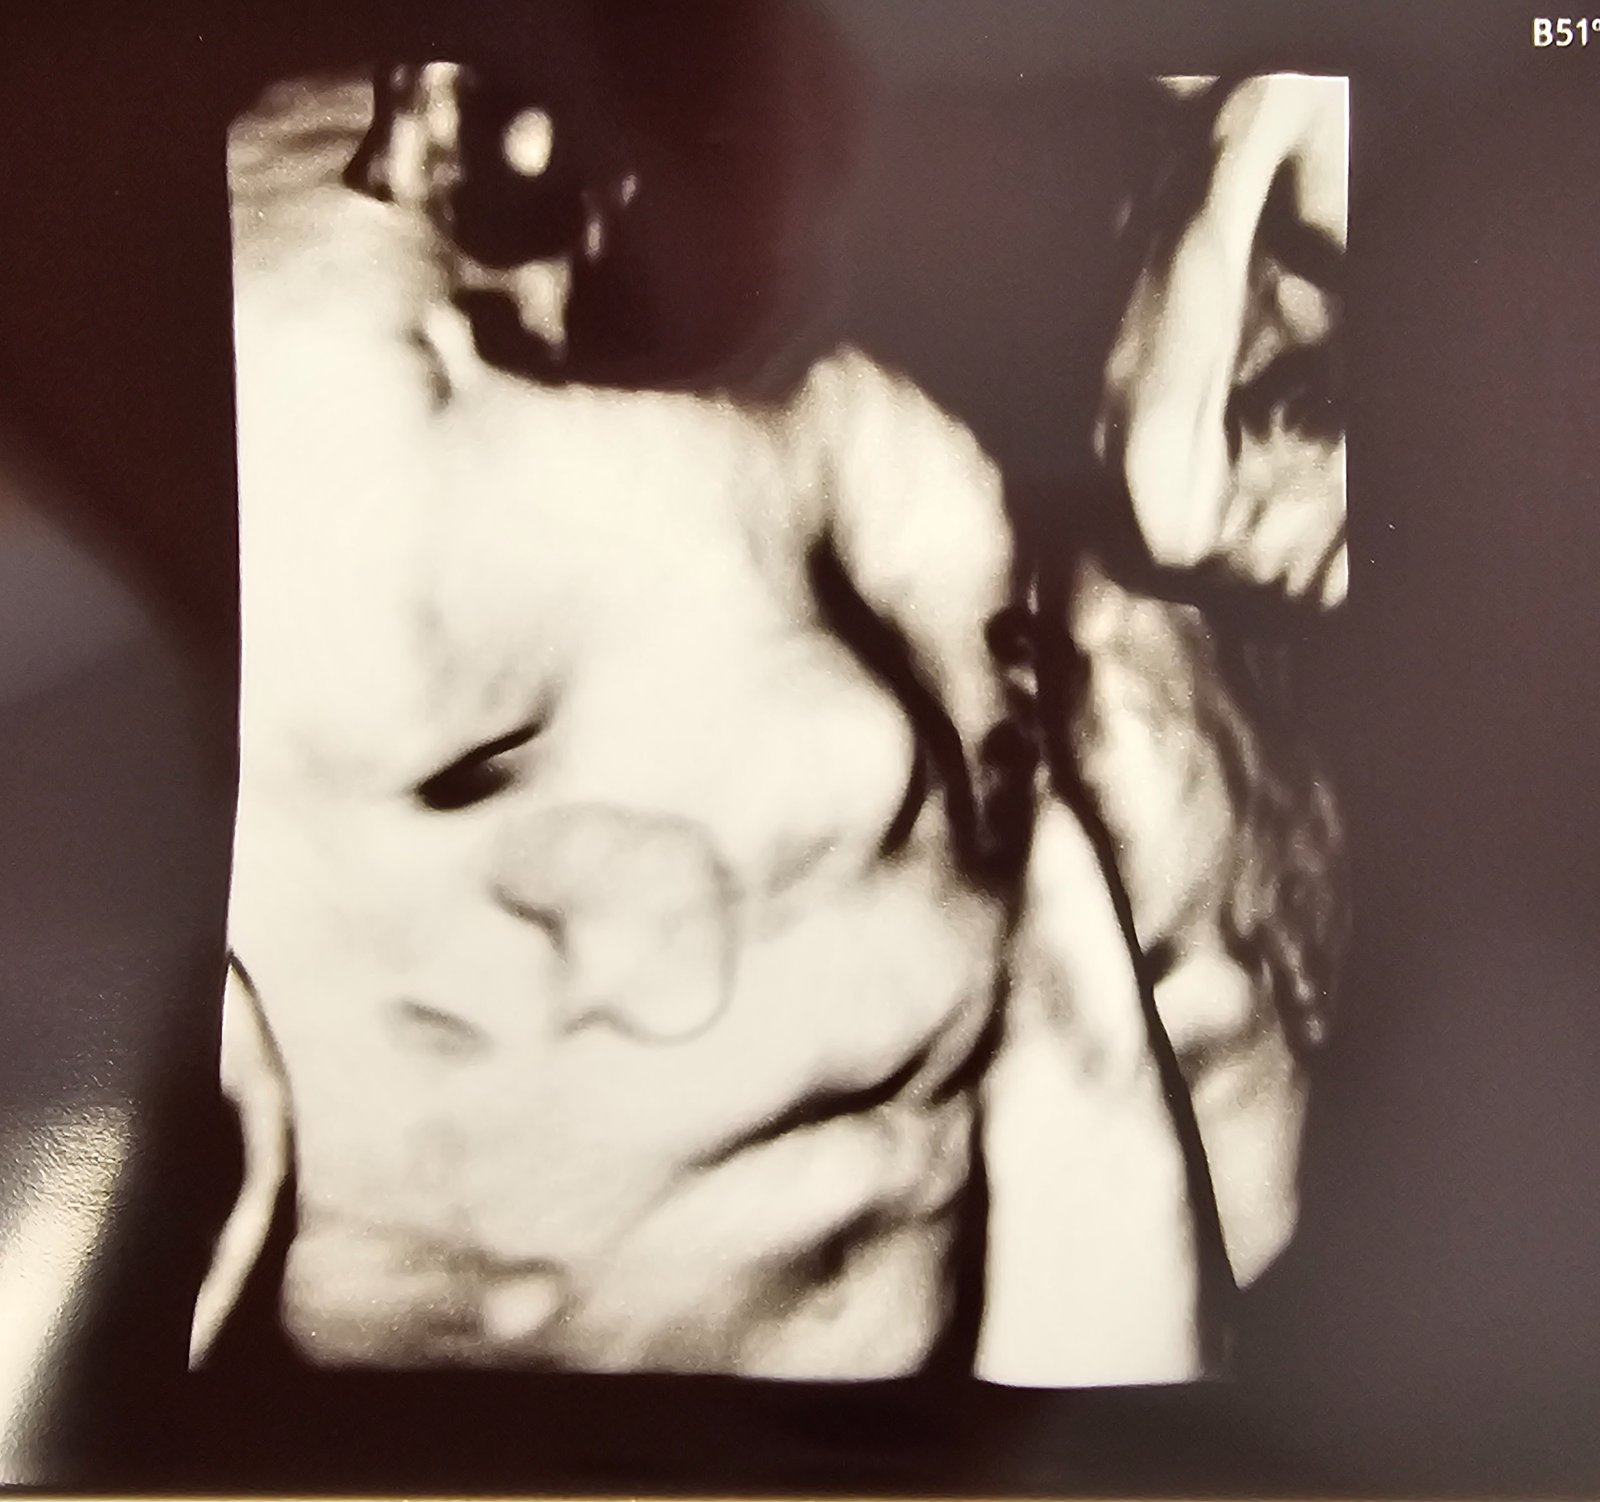

@alexandra_saska podla mna sa neskutocne podoba na mladsieho syna 😍 Tu mal 4 dni, taka cecka mala, ma uplne jeho pery 😍

@anjelicek26 krásne pery majú.Aj moja mala pery ako po kyseline, ale mala chudu tváričku išla trocha skôr a mala nižšiu váhu, tak pery pôsobili mohutne.Aj máš už meno vybraté?

@anjelicek26 to je 3d ultrazvuk?